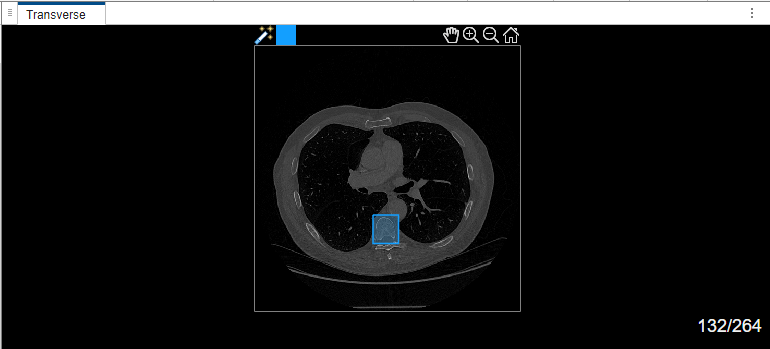

Select label Type1. Draw a bounding box around the object to segment in the transverse plane of the volume.

Once the MedSAM algorithm extracts the embeddings of the image, you can adjust the bounding box.

The MedSAM algorithm segments the object in the bounding box and labels it.